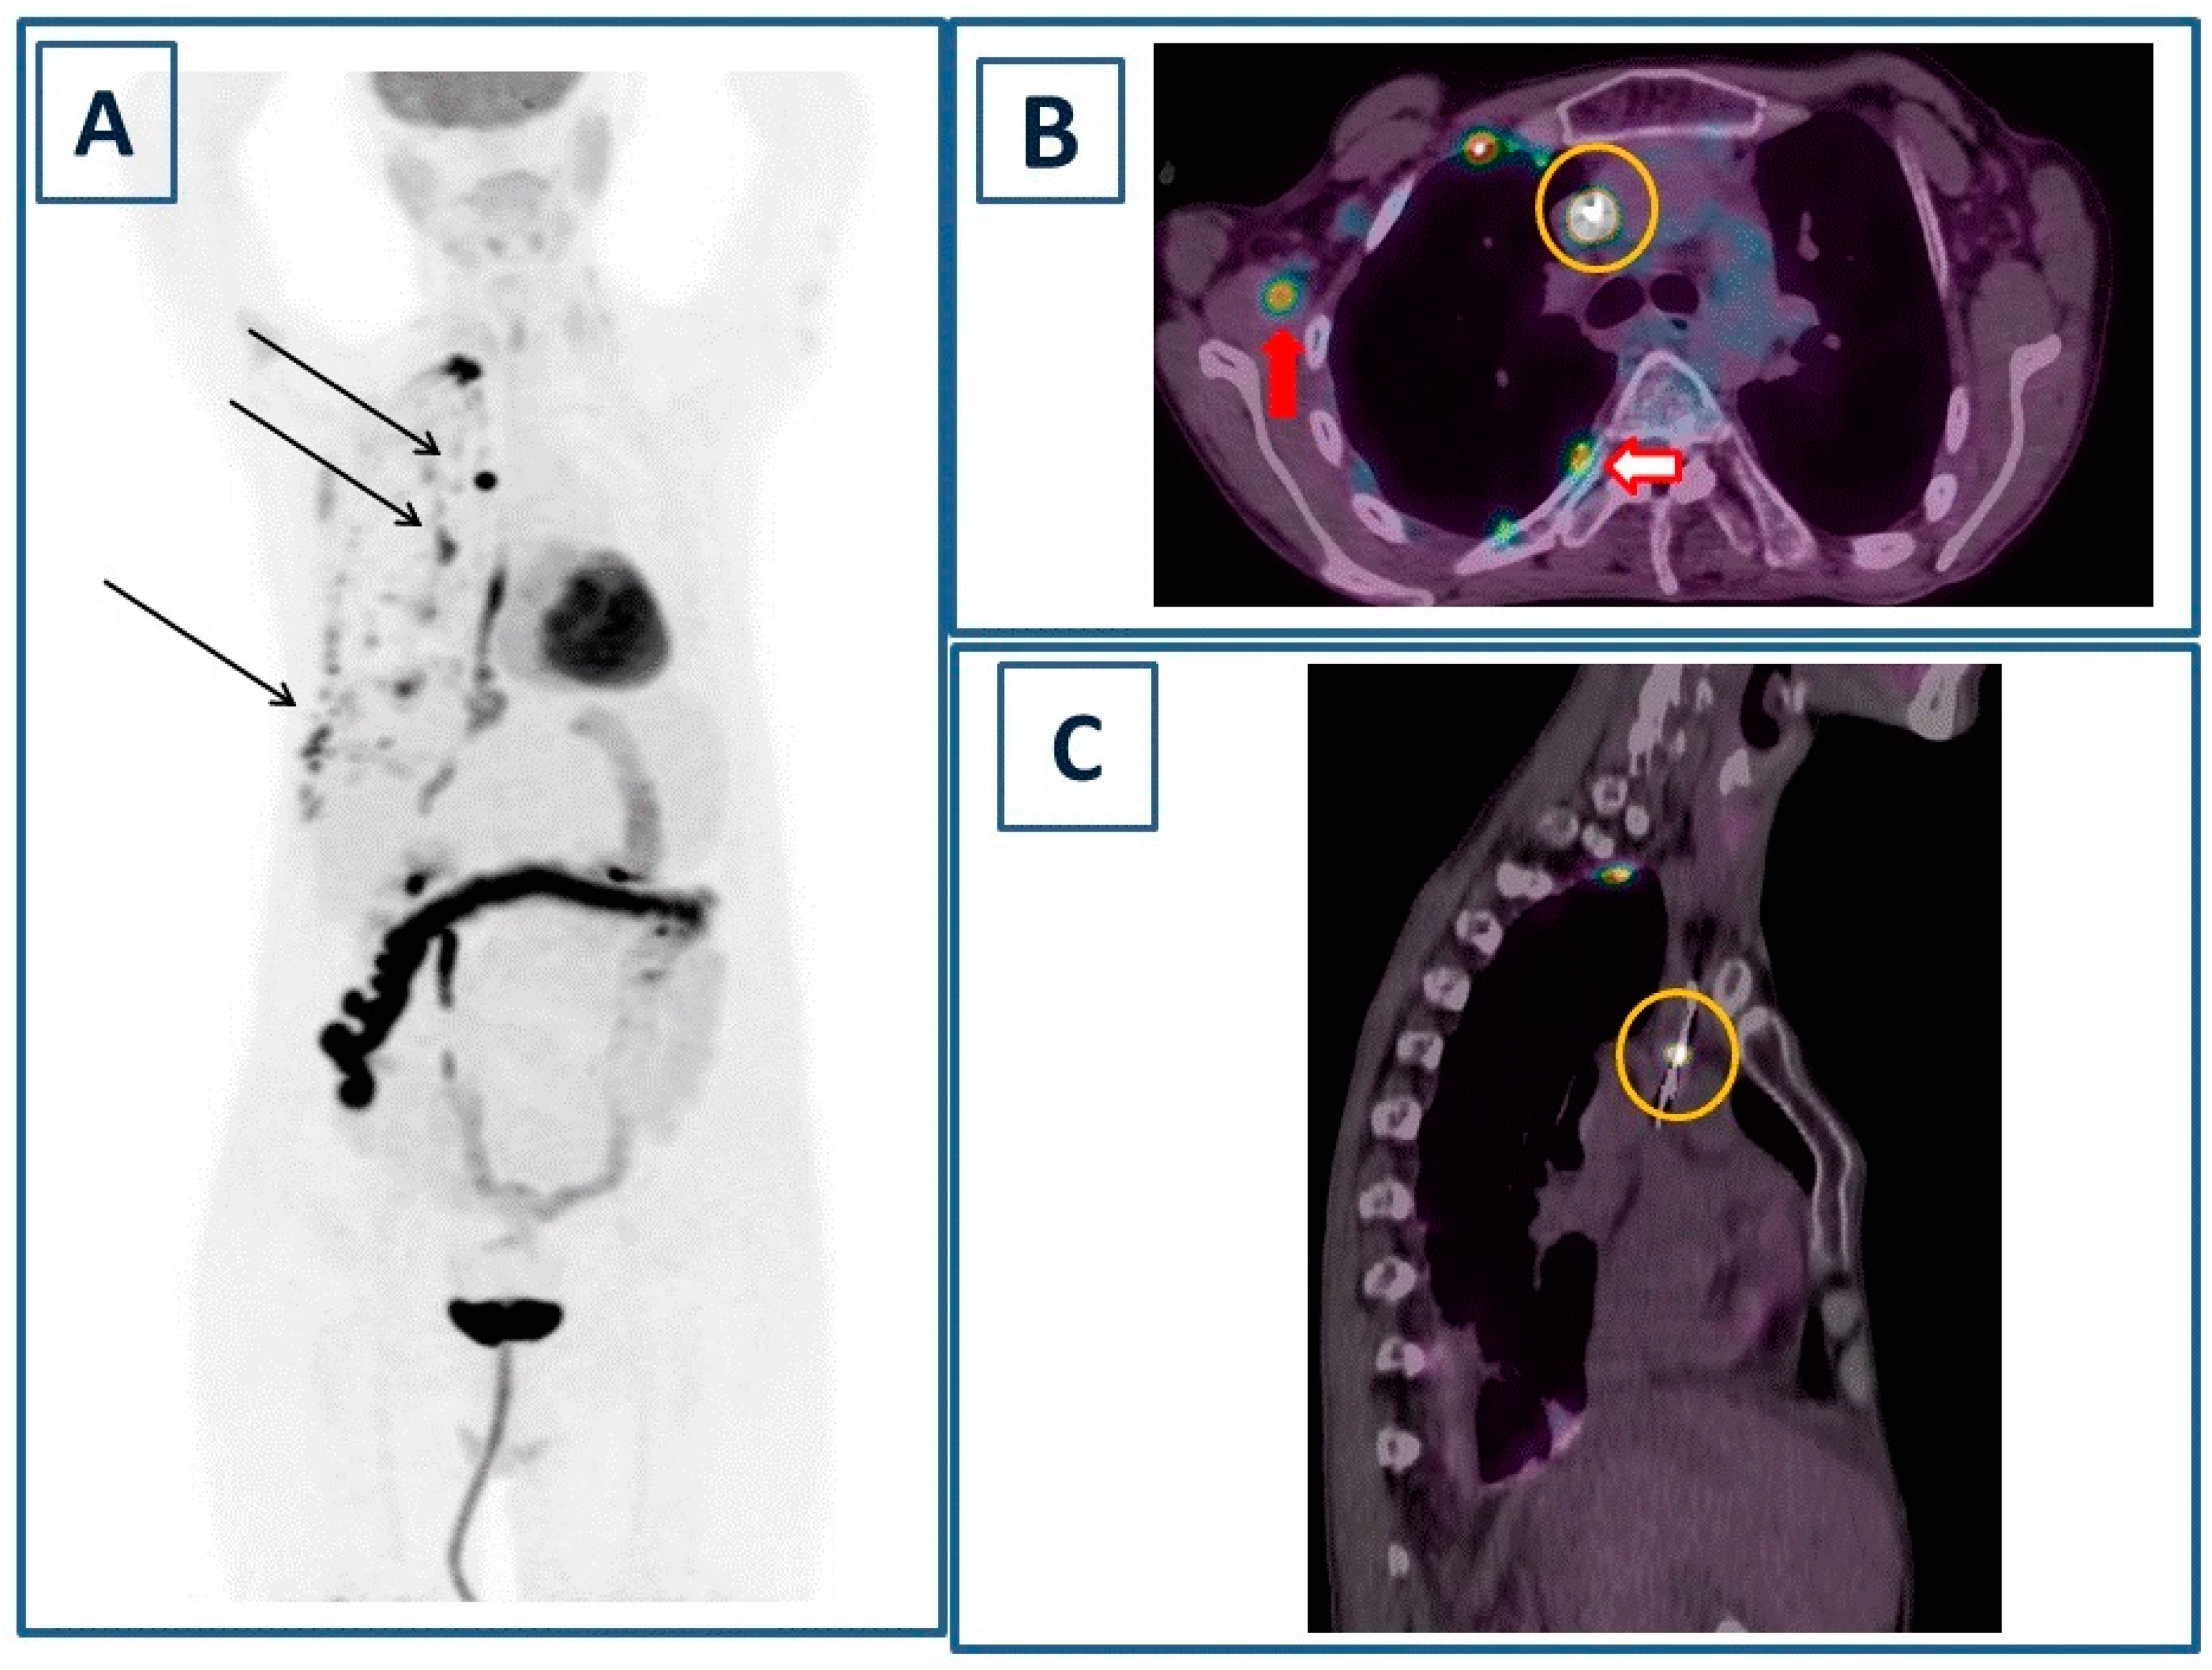

One Fell Swoop: Septic Muscle Embolism and Central Venous Catheter Infection Imaged with [18F] Fluorodeoxyglucose Positron Emission Tomography/Computed Tomography

Filippi, L.; Lacanfora, A.; Garaci, F. One Fell Swoop: Septic Muscle Embolism and Central Venous Catheter Infection Imaged with [18F] Fluorodeoxyglucose Positron Emission Tomography/Computed Tomography. Diagnostics 2024, 14, 180. https://doi.org/10.3390/diagnostics14020180